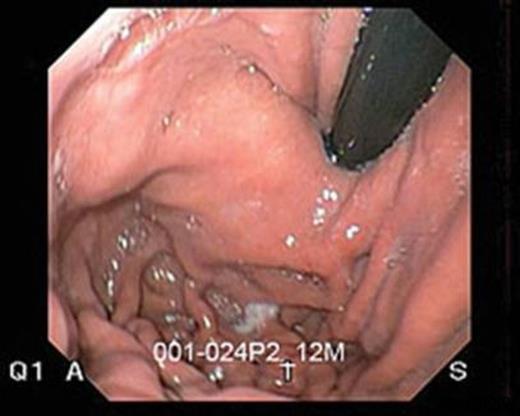

After a single transoral introduction of the instrument over the endoscope, the gastric fundus is retracted by a helical retractor. This creates a 3-4 cm long sleeve of tissue that is plicated by 6mm H-shaped polypropylene fasteners in a 200 to 300 degree fashion. Full thickness serosa-serosa plication at 1-2 cm above the gastro-esophageal junction begins with deployment of fasteners at the posterior and anterior side as visualized with the endoscope in the retroflexed view. Plication then continues at the greater curvature, 3-4 cm above the gastro-esophageal junction as the tissue is being pulled down. (Fig 3) By the end of the procedure (which typically takes 45-75 minutes), TIF increases the length of intra-abdominal esophagus, reduces small hiatal hernias, creates a 3-4cm GE valve and recreates the angle of His.

Full thickness serosa-serosa plication at 1-2 cm and 3-4 above the gastro-esophageal junction.